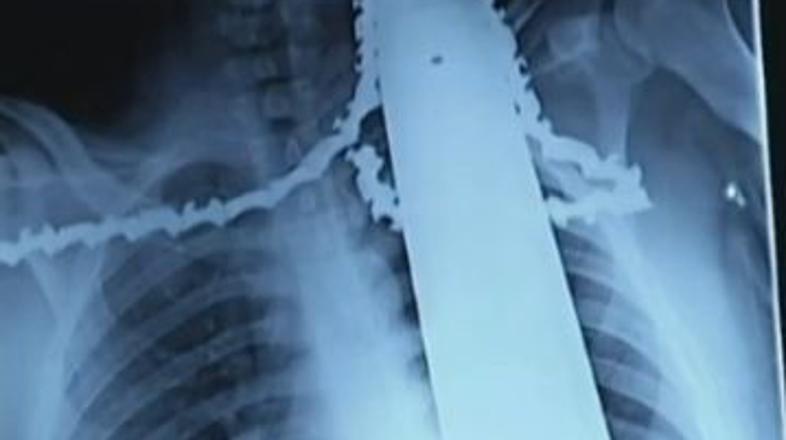

21-letni delavec se je ponesrečil z motorno žago, ki je pristala v njegovi rami in vratu.

Obrezovalec dreves James Valentine iz Pensilvanije je lahko srečen, da je živ. Med obrezovanjem drevja se mu je namreč motorna žaga nekaj centimetrov globoko zarila v ramo in vrat. Z žago v telesu so ga tudi pripeljali v bolnišnico.

Nesreča se je zgodila med običajnim delom na drevesih. V nekem trenutku je žaga poskočila nazaj in zarezala v njegovo telo. Delavci so nesrečneža spustili z drevesa, mu odstranili žago, rezilo pa pustili v telesu, da ne bi izgubil še več krvi. Nato so ga odpeljali v bolnišnico, kjer so ga takoj operirali.

"Bil je zelo razburjen, a ni bil v smrtni nevarnosti. Dobro se je držal, ni jokal in ni izgubil samonadzora," so povedali zdravniki. Na srečo je rezilo zgrešilo vse vitalne dele in je poškodovalo le ramenske mišice. Zdravniki pričakujejo, da bo popolnoma okreval.